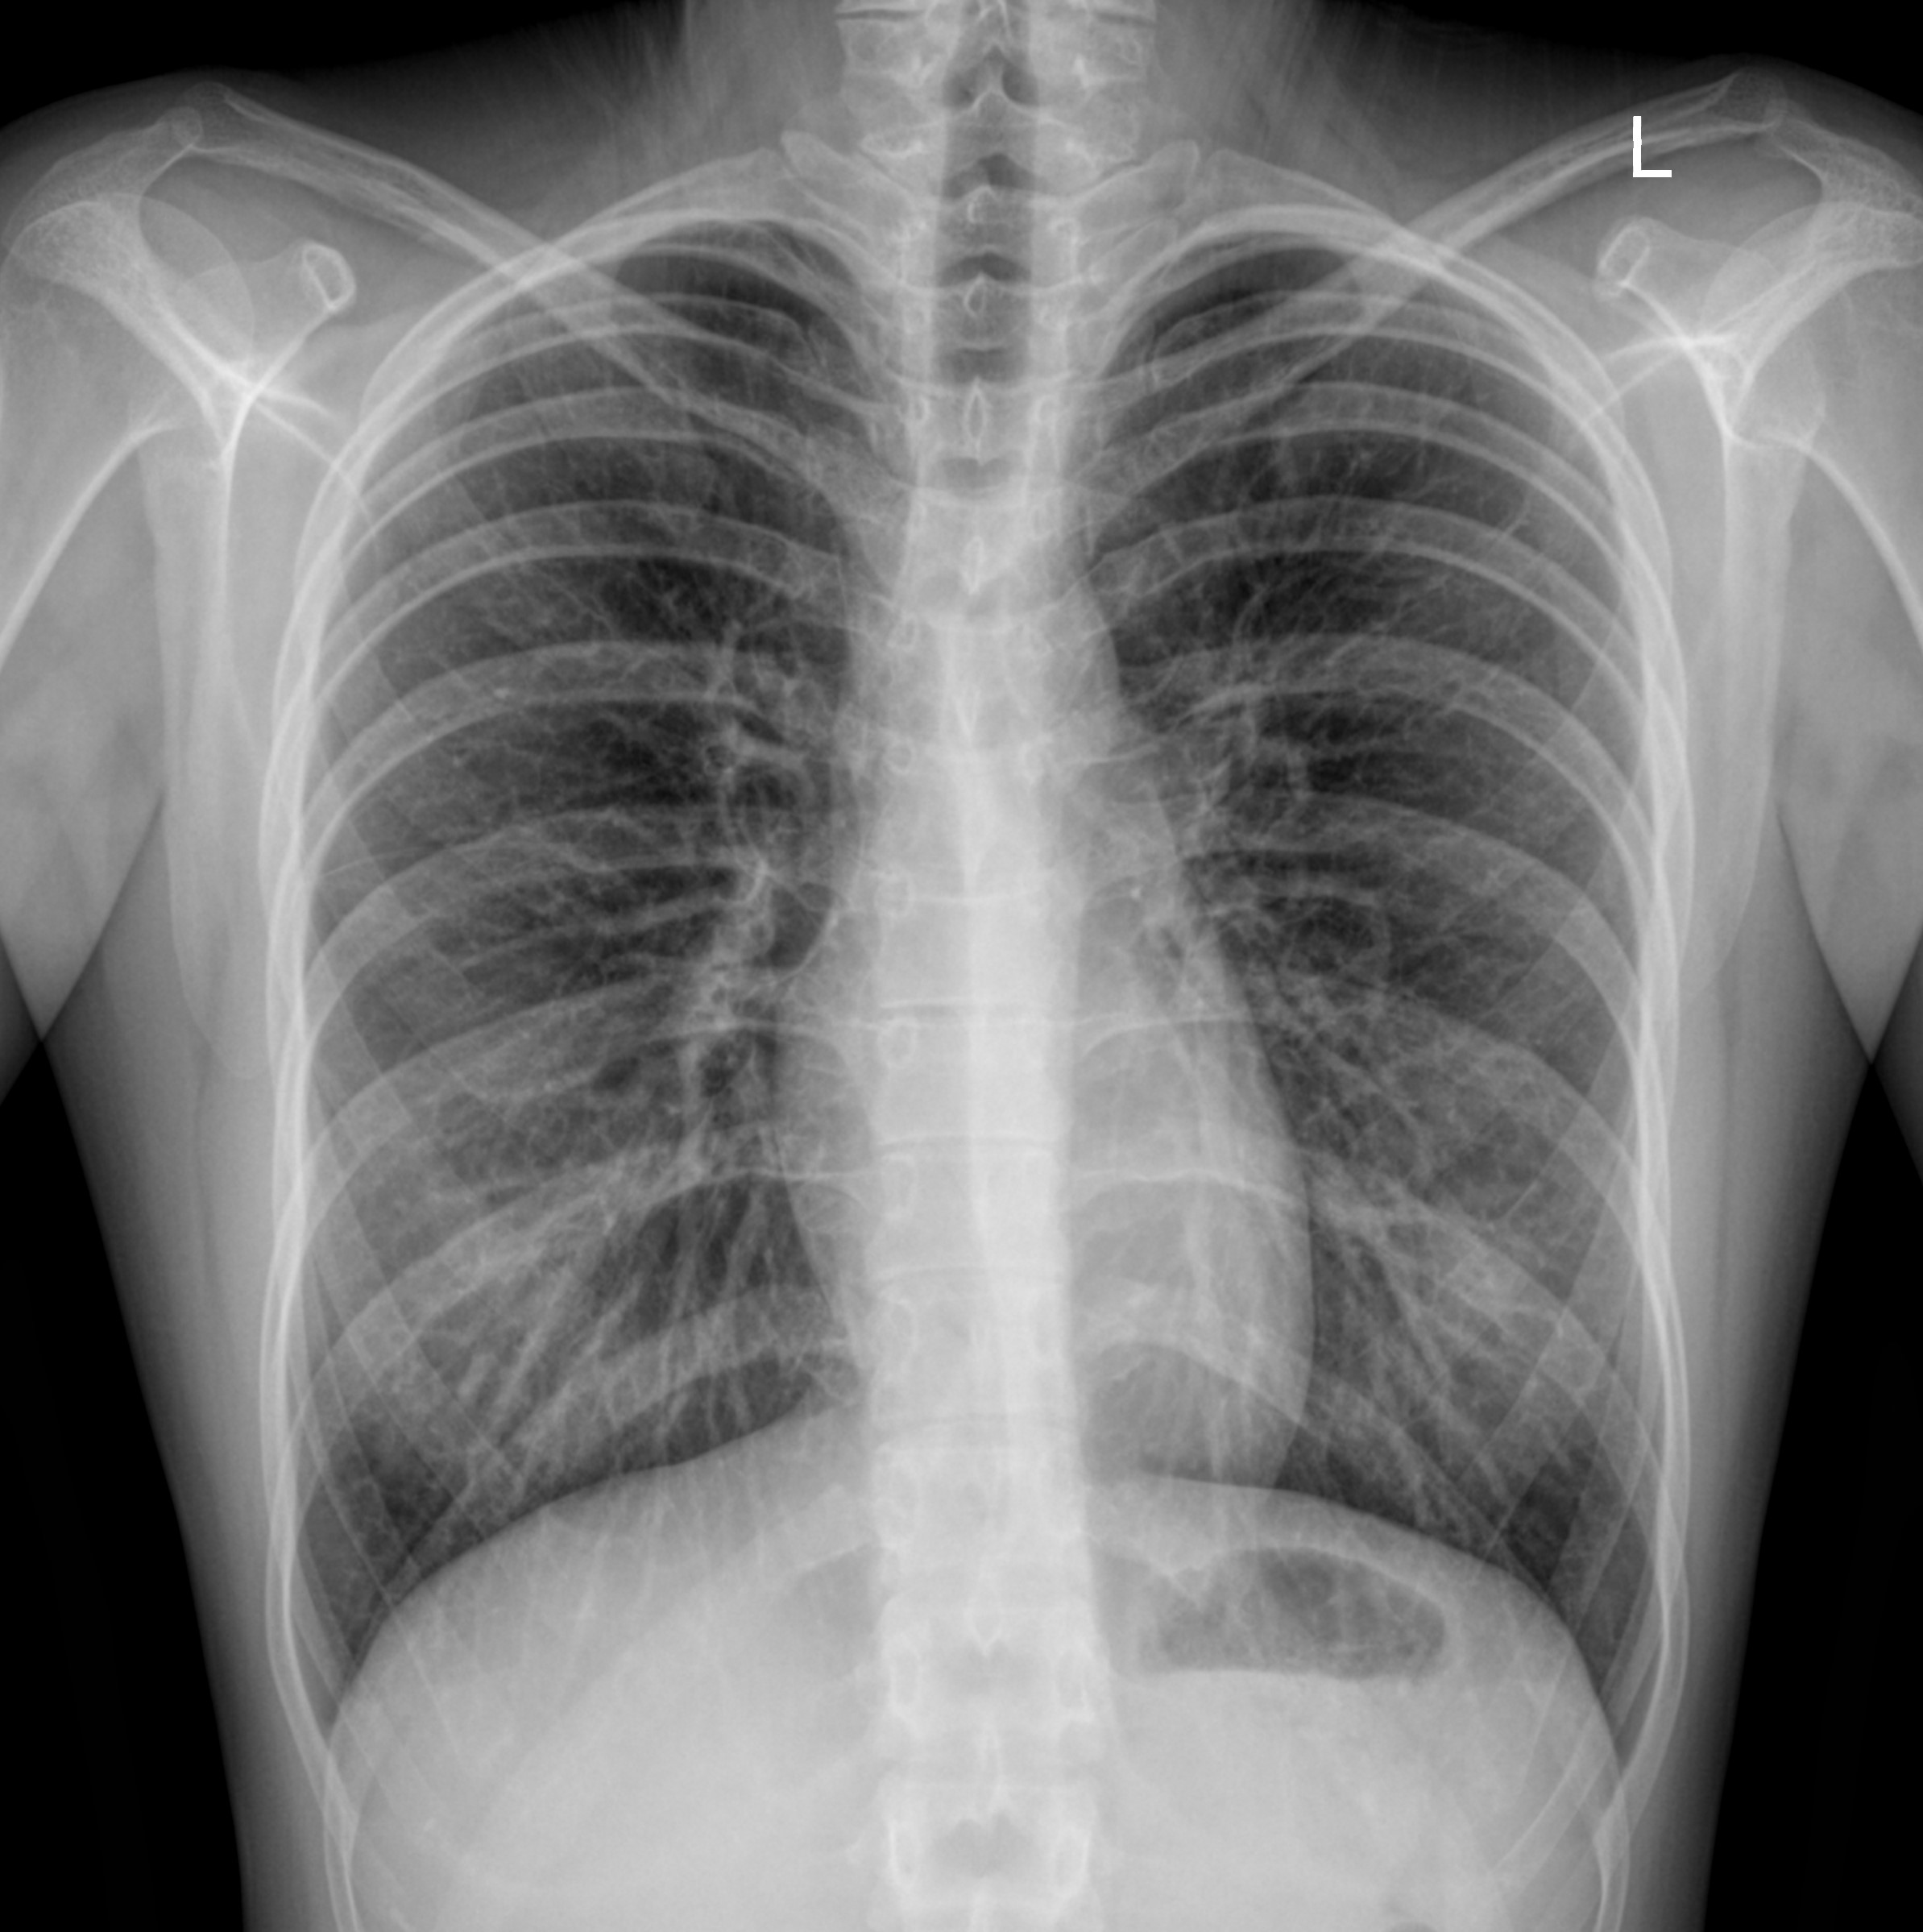

Так, начнем с рентгенографии. Данный метод исследования, как правило, используют для проведения обзорных исследований (скрининга), чтобы установить факт наличия патологии легочной ткани. В своей основе, такое исследование использует рентген-лучи и считывает разность прохождения данных лучей через структуры организма. Разность в прохождении лучей формируется за счет неоднородности плотностных характеристик структур организма. Рентгенография легких как правило делается в двух проекциях: фронтальной и боковой. На рентген-пленке хорошо видно наличие патологических изменений легочной системы (при пневмонии поражение легких 3 и 4 степени, туберкулез, плеврит и т.д.), а вот более мелкие патологические процессы скорее всего будут не визуализированы в виду феномена наложения теней от других органов.